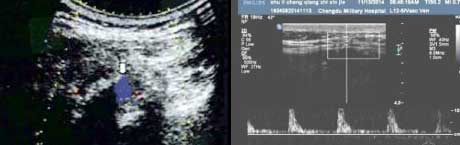

二、清晰显示滑膜炎性病变,提供早期骶髂关节病变线索

骶髂关节炎是强直性脊柱炎的显著特征,早期以滑膜炎性病变为主。肌骨超声对炎症血流十分敏感,可提示活动期强直性脊柱炎患者骶髂关节的异常血流增多变化,反映滑膜炎(滑膜增厚状况、滑膜形态表现、关节腔积液回声形态)表现,为活动性强直性脊柱炎早期骶髂关节病变提供重要线索。

血流信号

骶髂关节内部增厚的关节表面呈点状血流信号,可见多个小动脉点状血流信号。